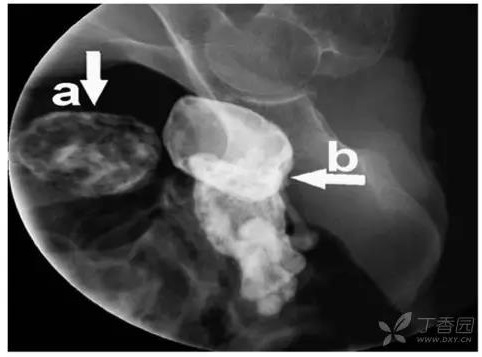

石胎的诊断

石胎的主要诊断手段是影像学检查,包括 B 超,X 线和 CT 等。超声下可见高回声光团和胎儿结构回声,X 线可以看到胎头、脊柱、肋骨及四肢等结构,CT 表现可见钙化的胎膜和胎儿(见下图)。

盆腔右侧石胎高密度影(X 线)

(图片来源:杨秀益,石胎 1 例报告,中国临床医学影像杂志 2014,25(8))

A 骨盆中钙化的囊性膜 B 石胎

(图片来源:Ahmet Selcuk,et al. Incidentally Detected Lithopedion in an 87-Year-Old Lady, Am J Forensic Med Pathol , 2016, 37(3):211-212)